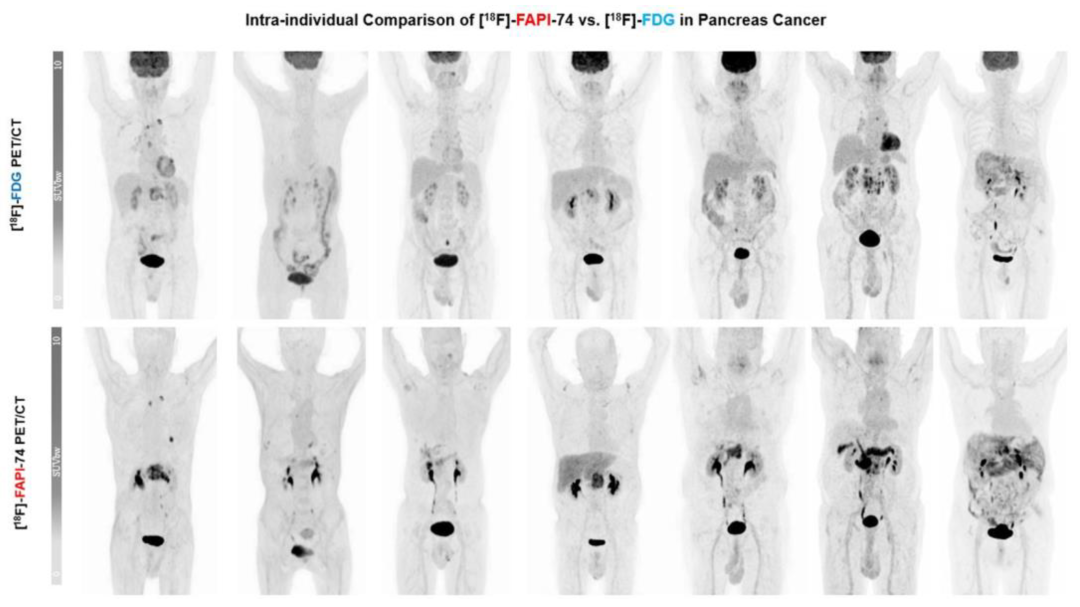

在FAPI靶向PET显像领域,多项研究证实68Ga-FAPI在多种癌症中的诊断效能优于18F-FDG。然而68Ga标记的FAPI存在一定局限性:其半衰期较短(约68分钟),单次制备活性产量有限,导致可注射患者数量较少;同时,68Ga的正电子能量较高,在一定程度上影响图像分辨质量。相比之下,18F作为临床最常用的PET核素,半衰期更长(约110分钟),便于通过回旋加速器规模化生产并实现远距离配送;此外,18F的正电子能量较低,有助于提升图像空间分辨率,因而被认为是更具应用潜力的PET成像核素。尽管18F的标记过程对操作技术有较高要求,但随着医用回旋加速器的普及,18F标记的示踪剂有望更广泛地推广应用,提升新型核医学显像技术的可及性。18F-FAPI-74作为一种18F标记的FAP靶向PET示踪剂,其在肿瘤原发灶及复发转移灶的诊断方面表现出了更为优越的灵敏度及准确性,为此,SOFIE持续加码该产品的商业化进程。